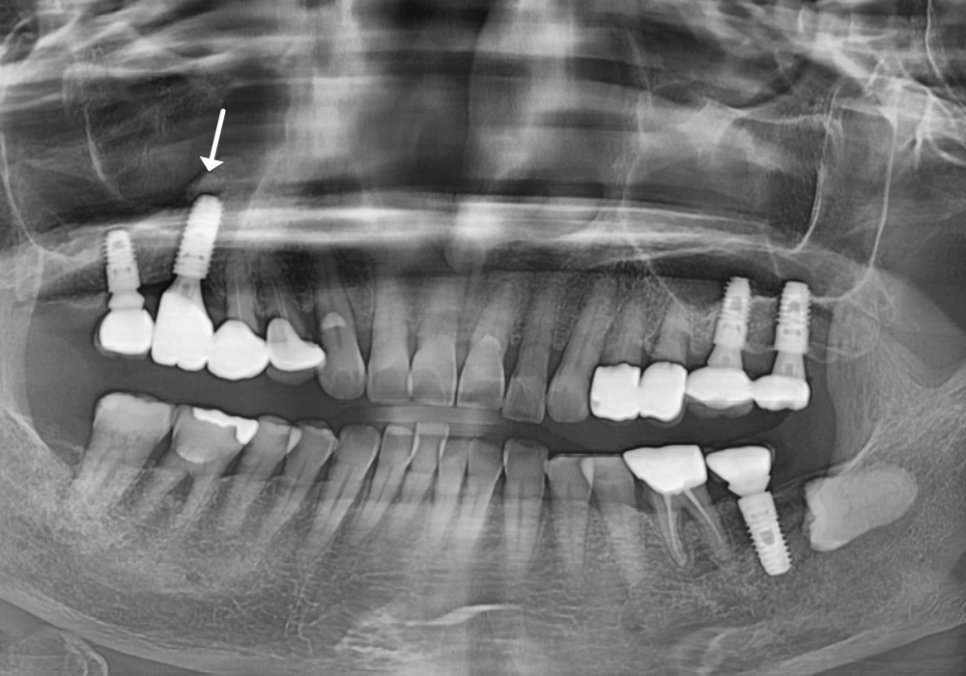

2개가 같이 묶여 있는 크라운의 해결 방법

잇몸 고름, 임플란트 주위염 재수술

이미 잇몸 뼈가 심각하게 녹아내린 상태라,

더 이상 유지는 불가능하다고 판단했습니다.

결국 문제가 된 임플란트를 제거 후

재수술하기로 결정했죠.

그런데 한 가지 난관이 있었습니다.

염증이 생긴 치아(#16)와

뒤쪽의 멀쩡한 치아(#17)가

하나로 단단히 묶여있었기 때문입니다.

231103

멀쩡한 보철물까지 뜯어내면

환자분의 비용 부담이 커지는 상황...

저는 쓸 수 있는 건 최대한 살리기 위해

'보철 컷팅'을 시도하기로 했습니다.

안쪽 금속 때문에 자르기도 힘들고,

자칫하면 도자기가 깨질 수 있는

아주 까다로운 작업이었죠.

혹시 모를 파절 위험성을 미리 설명드리고

숨죽여 조심스럽게 절단했습니다.

결과는? 다행히 파절 없이 깔끔하게 분리 성공!

문제 된 임플란트만 쏙 골라 안전하게 제거했습니다